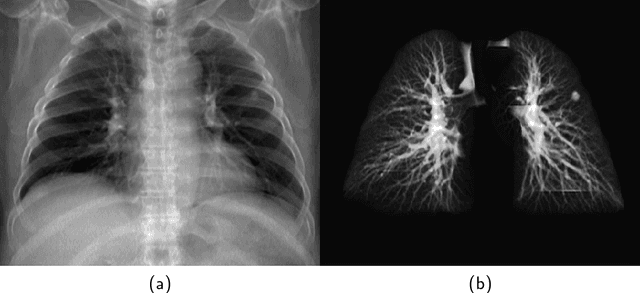

Abstract:The abundance of overlapping anatomical structures appearing in chest radiographs can reduce the performance of lung pathology detection by automated algorithms (CAD) as well as the human reader. In this paper, we present a deep learning based image processing technique for enhancing the contrast of soft lung structures in chest radiographs using Fully Convolutional Neural Networks (FCNN). Two 2D FCNN architectures were trained to accomplish the task: The first performs 2D lung segmentation which is used for normalization of the lung area. The second FCNN is trained to extract lung structures. To create the training images, we employed Simulated X-Ray or Digitally Reconstructed Radiographs (DRR) derived from 516 scans belonging to the LIDC-IDRI dataset. By first segmenting the lungs in the CT domain, we are able to create a dataset of 2D lung masks to be used for training the segmentation FCNN. For training the extraction FCNN, we create DRR images of only voxels belonging to the 3D lung segmentation which we call "Lung X-ray" and use them as target images. Once the lung structures are extracted, the original image can be enhanced by fusing the original input x-ray and the synthesized "Lung X-ray". We show that our enhancement technique is applicable to real x-ray data, and display our results on the recently released NIH Chest X-Ray-14 dataset. We see promising results when training a DenseNet-121 based architecture to work directly on the lung enhanced X-ray images.